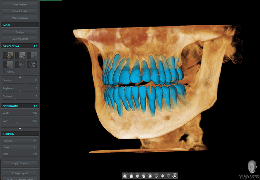

ART-Plan™ Artificial Intelligence Contouring